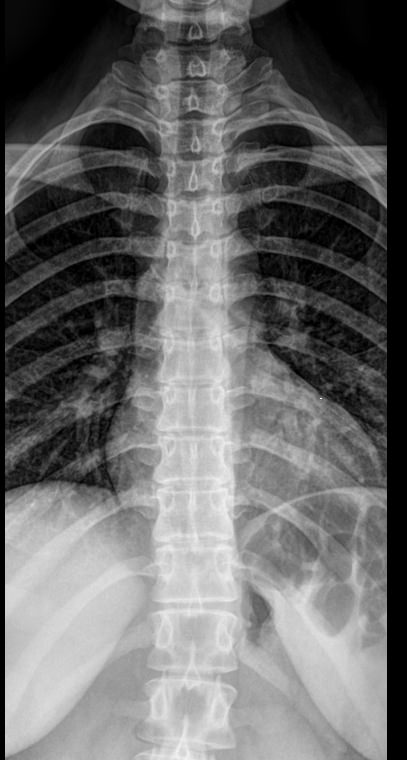

Рентгеновское исследование ― один из основных видов диагностики и первое, что назначают при подозрении на патологию грудного отдела позвоночника. На снимки попадают: 7-й шейный и все 12 грудных позвонков, а также частично ребра и ключицы. Диагностика всегда выполняется в 2 проекциях. Костные образования отчетливо видны и дают возможность определить патологические изменения и назначить необходимое лечение.